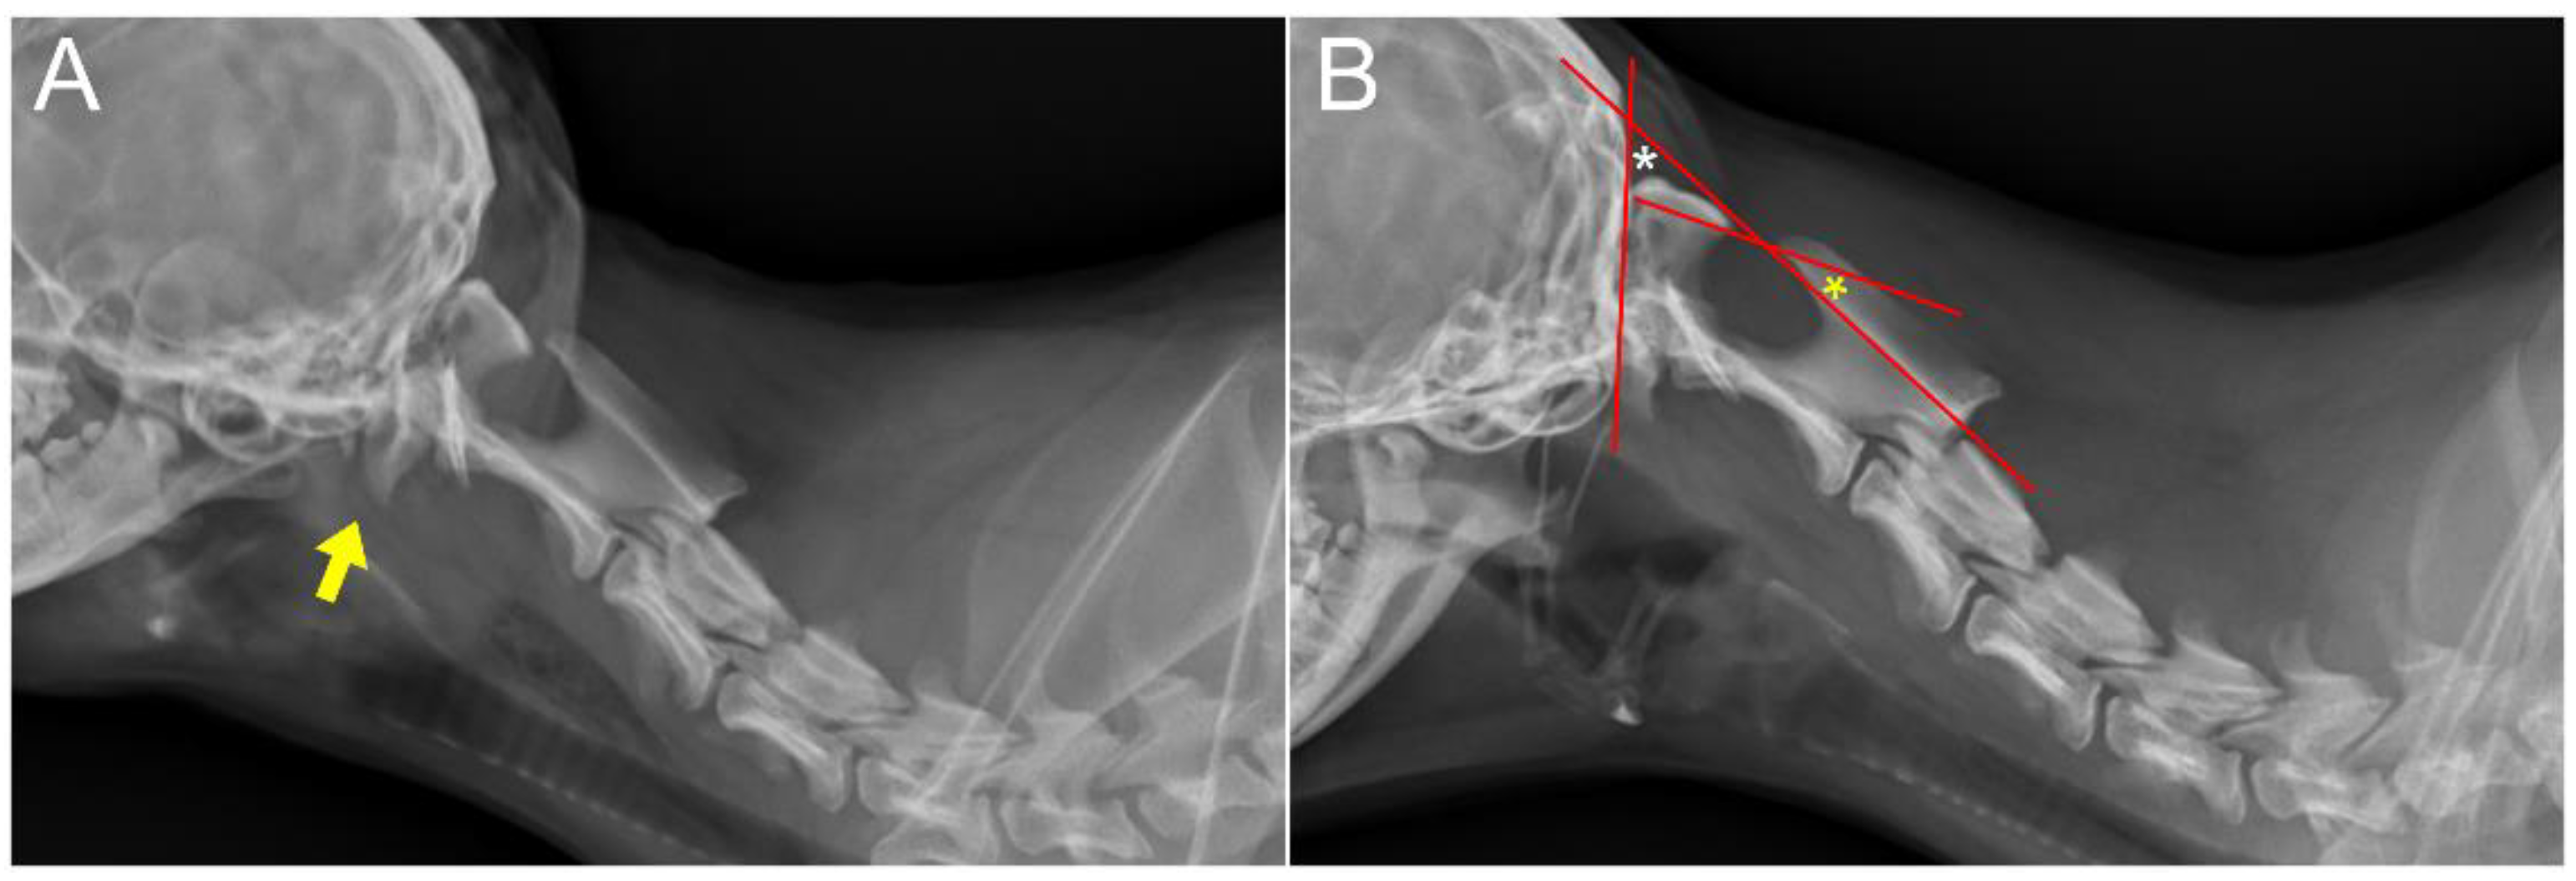

2. Case Description